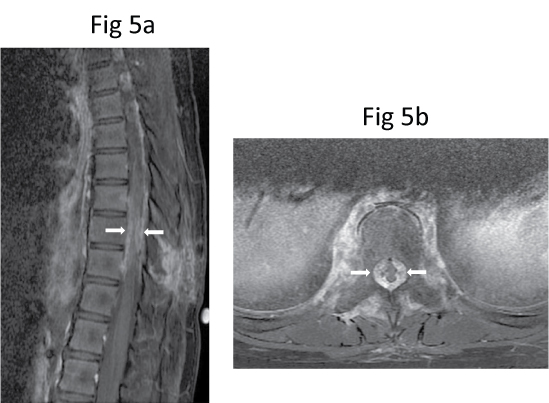

Six days after the biopsy, she developed significant sudden progressive worsening of bilateral lower limbs power, requiring support to walk, and one day of bowel incontinence. Urgent repeat MR imaging showed further mass effect on the thecal sac and the spinal cord by a soft tissue component, resulting in a slit-like appearance of the spinal cord (Figure 5). Computed tomography (CT) of the thorax performed later for staging did not show evidence of pulmonary metastasis. On CT, the lesion consisted of sclerosis of the entire T9 vertebral body with patchy but extensive mineralisation of the surrounding soft tissue components including the paravertebral, epidural and foraminal soft tissues (Figure 6). These features were difficult to assess on MR imaging.

Figure 5: Repeat (a) Sagittal and (b) Axial post-contrast fat-saturated T1-W MR images show further progression of the soft tissue component, resulting in more severe compression of the spinal cord (arrows). View Figure 5